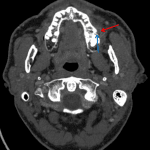

Indication: Left parotiditis

Findings

- Periapical lucency involving the left first maxillary molar with adjacent cortical breakthrough. Small adjacent peripherally enhancing fluid collection along the buccal aspect of the maxilla

- Moderate mucosal thickening of the left maxillary sinus. Mild mucosal thickening of the right maxillary sinus

- Normal parotid glands

Diagnosis

- Subperiosteal abscess

Periapical lucency involving the left first maxillary molar with adjacent cortical breakthrough and a small subperiosteal abscess measuring x by x.

Left greater than right maxillary sinus disease, likely odontogenic in origin.

No evidence of acute parotiditis.